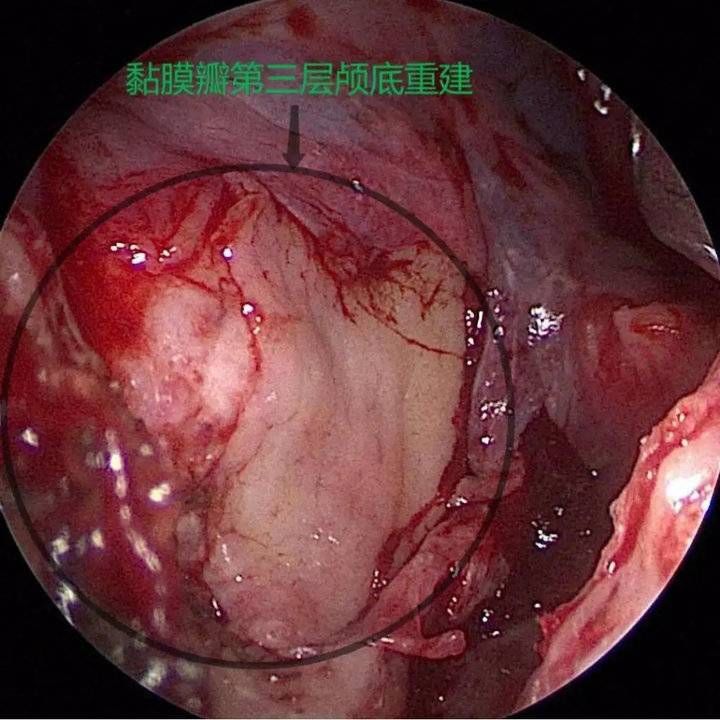

经呼吸科、麻醉科、耳鼻喉科及重症医学科评估后,8月4日,赵秋良主任团队为患者进行了鼻内镜下脑膜脑膨出切除+脑脊液修补+颅底重建手术。赵秋良主任介绍,这是全市首例鼻内镜下脑脊液修补手术,是鼻科鼻内镜微创手术里难度系数最高的四级手术之一,该手术充分利用人体自然腔道,全程在高清屏幕直视下完成,创伤小、愈后良好,术后并发症少,脑脊液修复的成功率高达90%。